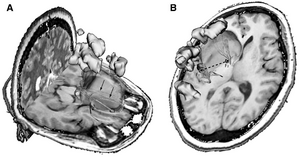

Publication: World Neurosurg. 2015 Dec 27. PMID: 26732948

Institution: Department of Neurosurgery, People's Liberation Army General Hospital, Beijing, China. Background/Purpose: OBJECTIVE: To investigate the feasibility and reliability of virtual endoscopy (VE) as a rapid, low-cost and interactive tool for suprasellar arachnoid cysts (SACs) diagnosis and surgical planning. Methods: 18 SACs patients treated with endoscopic ventriculocystostomy were recruited, and same number of endoscopic third ventriculostomy treated patients was randomly selected as VE reconstruction control group. After loading their DICOM data into free software 3D Slicer, VE reconstruction was independently performed by 3 blinded clinicians and the time required for each reconstruction was recorded. Other 3 blinded senior neurosurgeons interactively graded the visibility of VE by watching video recordings of endoscopic procedures. Based on the visibility scores, Receiver Operating Characteristic (ROC) curve analysis was used to investigate the reliability of VE to diagnose SACs, and the Bland-Altman plot was employed to assess the VE's reliability for surgical planning. In addition, intra-class correlation coefficient (ICC) was calculated to estimate the consistency among the results of 3 reconstructing performers. Results: All 3 independent reconstructing performers successfully completed VE simulation for all cases, and the average reconstructing time was 10.2±9.7 minutes. The area under ROC curve of cyst's visibility score was 0.96, implying its diagnostic value of SACs. Bland-Altman plot indicated good agreement between VE and intraoperative viewings, suggesting the VE's anatomical accuracy for surgical planning. In addition, ICC was 0.81, which revealed excellent inter-performer consistency of our simulation method. Conclusion: This study substantiated the feasibility and reliability of VE as a rapid, low-cost and interactive modality for SACs diagnosis and surgical planning. |